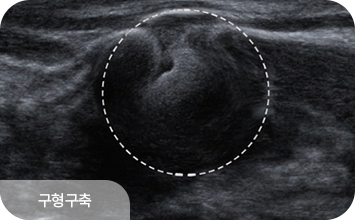

유방 확대술(보형물 삽입) 후에도 초음파 검진은 동일하게 시행할 수 있으며,

보형물 위의 유방 조직을 꼼꼼히 관찰하여 종괴나 이상 소견을 확인합니다.

보형물 자체의 파열이나 누출 여부도 초음파로 평가할 수 있어,

수술 후에도 정기적인 초음파 검진이 중요합니다.